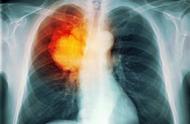

抗癌卫士告诉你如何检查癌症十大症状,提醒大家注意。1、久咳不愈,小心肺癌持续性咳嗽可能在提示你是肺癌的早期症状,发热、咳嗽、声音嘶哑、发热等常见呼吸道症状也可能是肺癌。